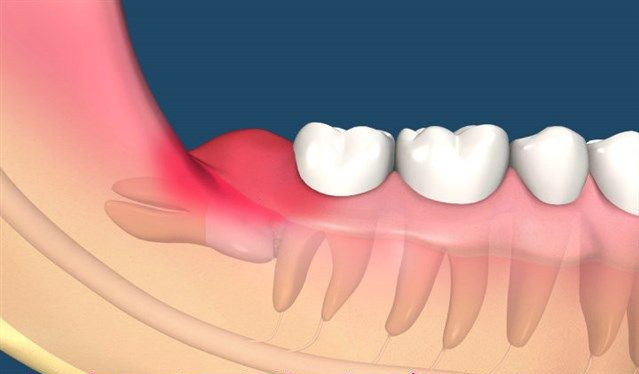

2、經常引起牙齦腫痛的智齒冠周炎的情況,可以考慮拔除。

3、位置不對,比如橫著長,歪著長的智齒建議拔除。